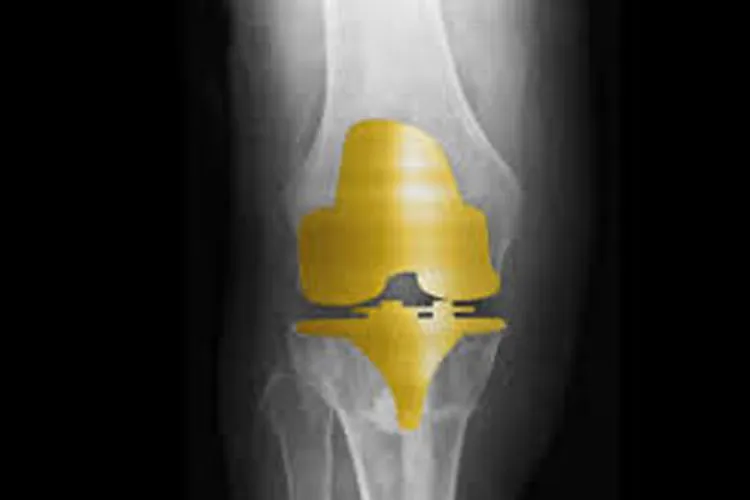

4. देश में तेजी से बढ़ रहा 'गोल्डन नी इंप्लांट' का चलन, सिर्फ 1 घंटे में सर्जरी

देश में तेजी से बढ़ रहा 'गोल्डन नी इंप्लांट' का चलन, सिर्फ 1 घंटे में सर्जरी

हेल्थ डेस्क: देश में घुटने बदलने की सर्जरी में 'गोल्डन नी इंप्लांट' का उपयोग तेजी से बढ़ने लगा है। पिछले करीब ढाई महीने के भीतर अकेले इंद्रप्रस्थ अपोलो अस्पताल में ही 25 मरीजों की 'गोल्डन नी इम्प्लांट' सर्जरी हुई है। अस्पताल के वरिष्ठ आर्थोपेडिक एवं ज्वाइंट रिप्लेसमेंट सर्जन डॉ. राजू वैश्य ने कहा, "इस साल 26 मई को अस्पताल में पहली गोल्डन नी इंप्लांट सर्जरी की गई थी और तब से लेकर अब तक करीब 25 गोल्डन नी इंप्लांट सर्जरी हो चुकी है। इस सर्जरी में एक घंटे का समय लगता है।"